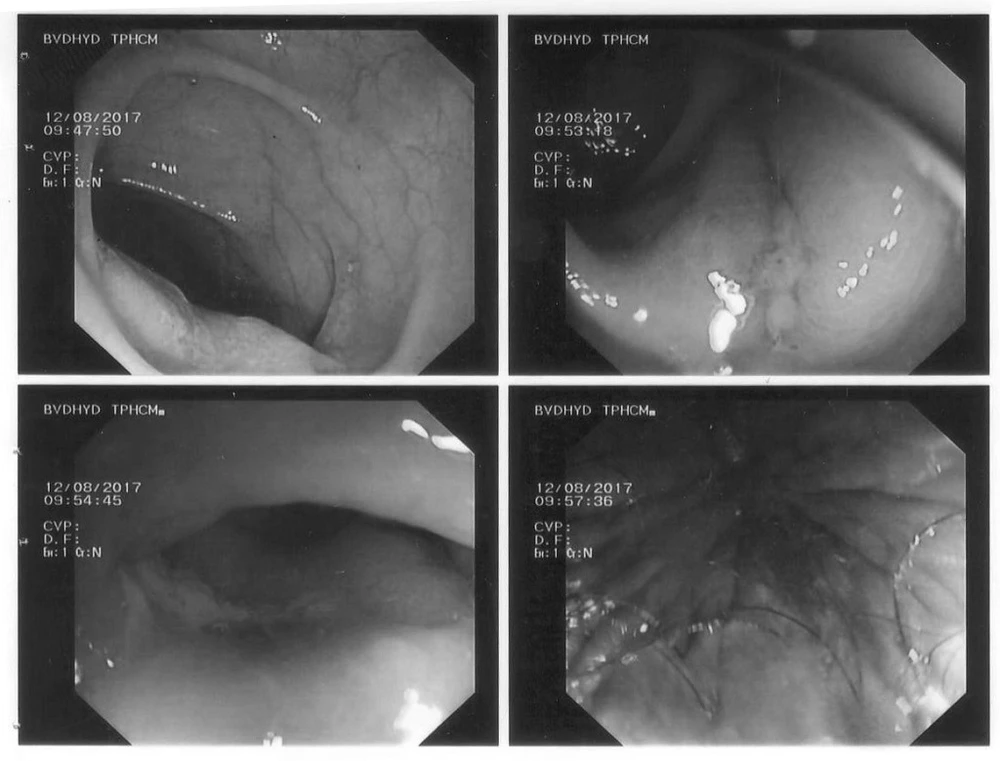

Theo ThS BS. Phạm Công Khánh – Phó trưởng khoa Nội soi BV ĐHYD, nhờ ứng dụng phương pháp mới, người bệnh được điều trị polyp lớn nghi ung thư hóa bằng kỹ thuật cắt niêm mạc (EMR – Endoscopic Mucosal Resection) qua nội soi đại tràng không cần phẫu thuật. Ba polyp lớn ở đại tràng chậu hông và trực tràng được cắt hoàn toàn, không tai biến chảy máu hay các tai biến khác.

Kết quả bệnh lý polyp ở trực tràng là polyp ung thư ở bề mặt được cắt hoàn toàn qua nội soi, không cần phải phẫu thuật thêm. Sau khi điều trị polyp ung thư hóa ở trực tràng và đại tràng chậu hông, người bệnh được phẫu thuật cắt đại tràng phải để điều trị ung thư đại tràng ngang. Hiện tại, người bệnh đã bình phục và xuất viện.

Từ tháng 8-2017, Khoa Nội soi Bệnh viện Đại học Y Dược TPHCM (BV ĐHYD) đã triển khai thành công điều trị ung thư sớm trực tràng bằng kỹ thuật cắt niêm mạc qua nội soi đại tràng mà không cần phẫu thuật. Kỹ thuật cao được thực hiện an toàn trên người bệnh có nhiều bệnh nội khoa nặng và phức tạp, đặc biệt là đang dùng thuốc kháng đông. Lợi ích mang lại giúp bảo tồn được trực tràng và phần lớn đại tràng cho người bệnh có đa polyp đại trực tràng, đặt biệt là polyp ung thư hóa, góp phần nâng cao chất lượng cuộc sống cho người bệnh.